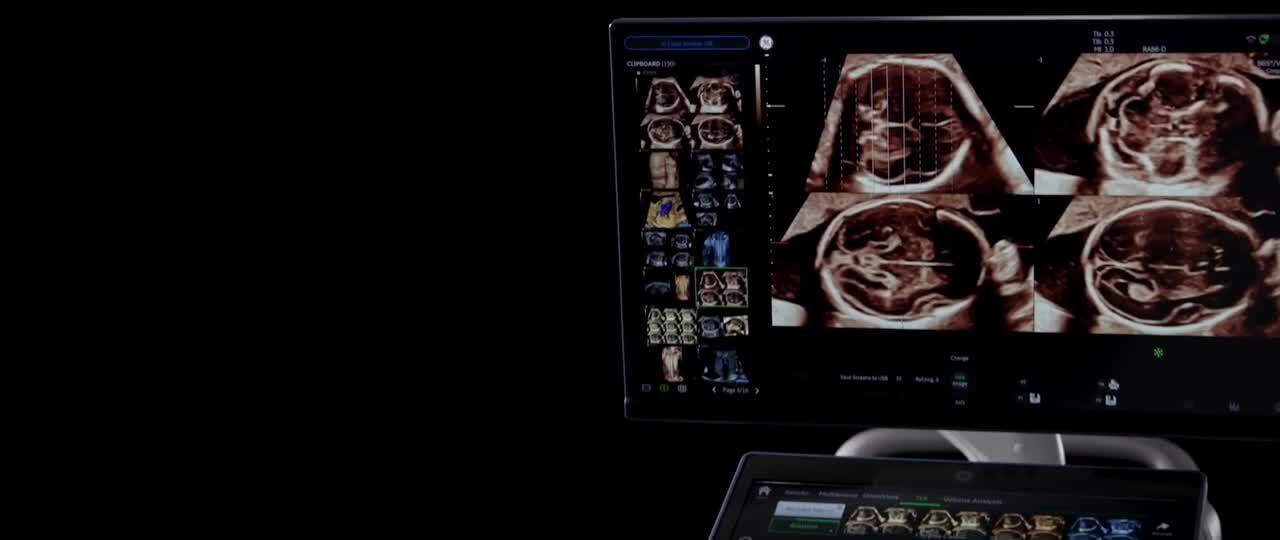

Generate spectacular 2D/3D and color Doppler images with increased penetration and stunning clarity, to help visualize critical details needed for diagnostic assurance. The Lyric Architecture unlocks new imaging and processing power to expand your imaging capabilities for years to come

The Lyric Architecture delivers the most progressive and adaptive capabilities to achieve high resolution, detailed images